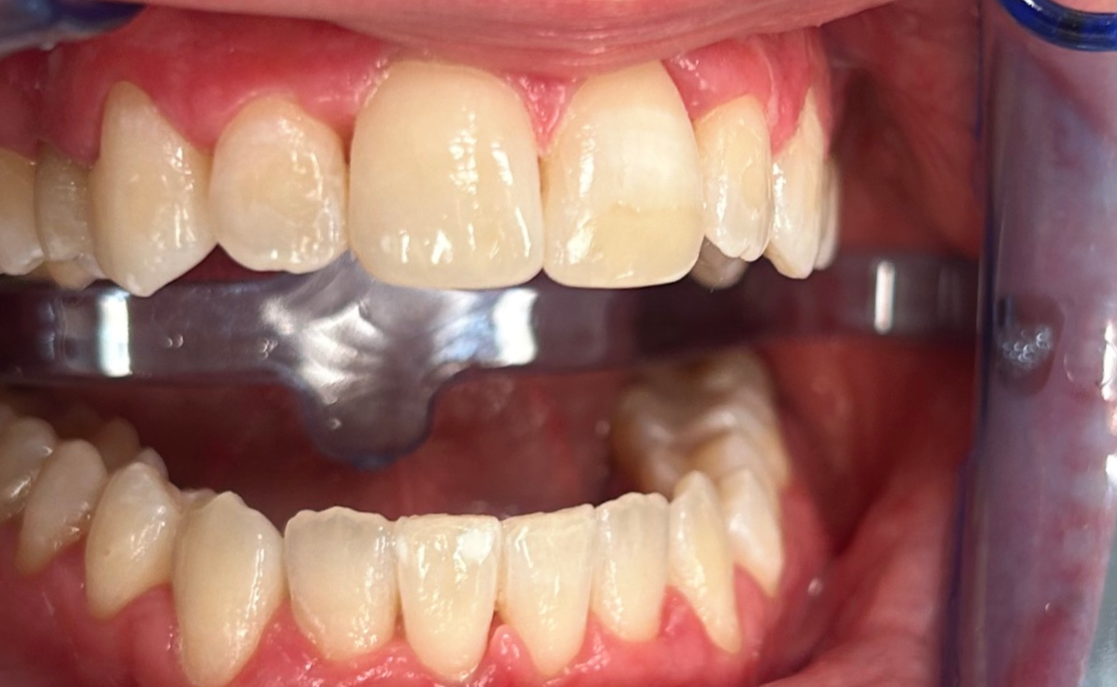

Zaprezentujemy serię poruszających historii pacjentów, którzy zdecydowali się na kompleksowe leczenie dentystyczne. Od przypadków zaawansowanej próchnicy, przez wypadki, które wymagały rekonstrukcji zębów, po pacjentów marzących o hollywoodzkim uśmiechu dzięki zastosowaniu licówek – każda historia jest dowodem na to, jak nowoczesna stomatologia może odmienić życie.

Skupimy się na innowacyjnych technologiach i metodach leczenia stosowanych w naszej klinice, które sprawiają, że te metamorfozy są możliwe. Od cyfrowego projektowania uśmiechu (DSD), przez ortodoncję i implanty, po zaawansowaną chirurgię szczękowo-twarzową. Omówimy, jak te techniki pracują razem, aby osiągnąć najlepsze wyniki.